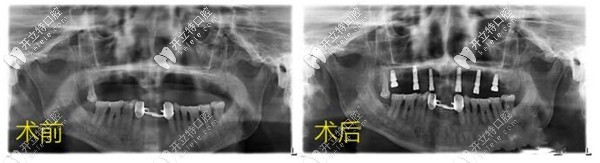

肖醫(yī)生通過(guò)多年的積累,熟練掌握口腔各項(xiàng)專(zhuān)業(yè)技能,尤其在牙齒種植修復(fù)領(lǐng)域著稱(chēng)。

工作中的肖院長(zhǎng),對(duì)帶顧客耐心負(fù)責(zé),對(duì)于不同的病例,能有效的制定出個(gè)性化的診療方案。據(jù)不完全統(tǒng)計(jì),二十年以來(lái),肖醫(yī)生診療的口腔病例已經(jīng)高達(dá)近萬(wàn)例。